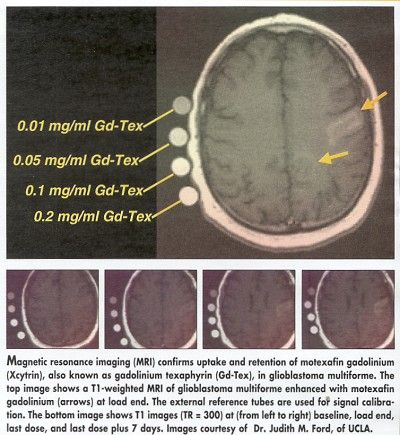

Judith M. Ford, MD, PhD, assistant professor of radiation oncology, UCLA Medical Center, said that median survival for the first 24 patients in the glioblastoma study was 17.3 months (abstract 213). She also reported that imaging studies showed the drug to be present in the tumor throughout the course of treatment, but not in normal brain tissue.

Thus far, Xcytrin’s behavior in children is similar to what has been documented in adults, Dr. Mehta said, and imaging shows the drug is entering the tumor but not normal tissue. He is optimistic that Xcytrin may improve survival for brainstem glioma, a rare but aggressive childhood brain tumor that is usually inoperable and has not responded well to chemotherapy.

In the glioblastoma trial reported by Dr. Ford, dose escalation is focused on delivering Xcytrin for a longer course of radiation (6.5 weeks) than was required for whole brain irradiation in the brain metastases trial (10 days). Dr. Ford said that patients tolerated 22 doses of 4 mg/kg without reaching dose-limiting toxicity.

She said that one patient stopped treatment because of a rash and fever, but imaging showed that the drug already administered remained present in the tumor.